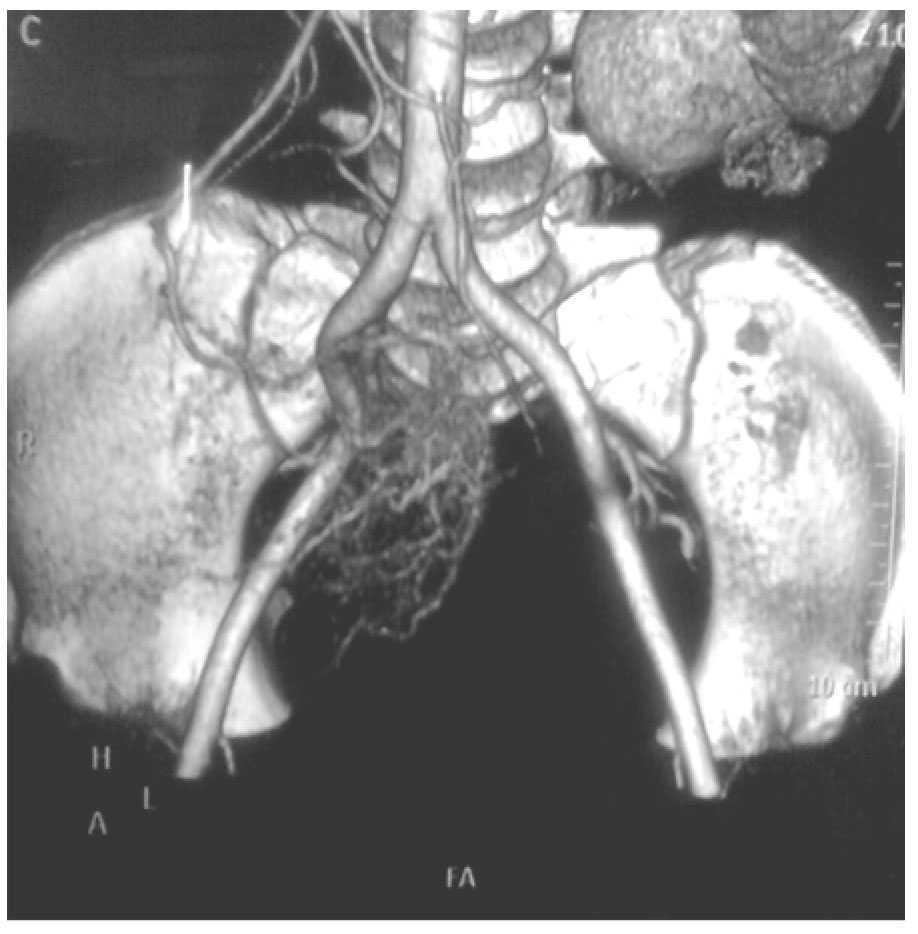

Mujer de 47 años, diabética e hipertensa de larga evolución, con antecedente de nefrectomía derecha por donación cinco años antes. Su padecimiento se inició a fines de 2008 con presencia de evacuaciones hematoquézicas y melena, por lo que requirió múltiples transfusiones. La endoscopia alta y colonoscopia no detectaron el sitio de hemorragia. En agosto de 2009 presentó choque hipovolémico secunadario a hematoquezia (hemoglobina de 3.5 g/dL) que requirió de transfusión de siete paquetes globulares. Se realizaron nuevamente endoscopia alta y colonoscopia que no detectaron en sitio de hemorragia. El gammagrama con eritrocitos marcados mostró concentración anormal del radioisótopo en la flexura hepática. Una enteroscopia no mostró sangrado evidente. Se practicó una angiografía selectiva de arteria mesentérica superior (AMS) en fase arterial (Figura 1), que mostró vasos de neoformación tortuosos e irregulares a nivel de íleon, sin retorno venoso temprano. La angio-tomografía computarizada (angioTC) con reconstrucción coronal y proyección de máxima intensidad (Figura 2), detectó una imagen hipodensa, con vasos tortuosos de neoformación que nacían de la AMS. La angioTC en 3D (Figura 3) reveló múltiples vasos de neoformación dependientes de la AMS localizados en íleon que demuestran una tumoración con gran vascularidad. Se realizó laparotomía exploradora encontrando un tumor a 90 cm de la válvula ileocecal (Figura 4). El análisis histopatológico determinó tumor estromal de alto grado con bordes quirúrgicos libres de lesión, con inmunohistoquímica para CD117 (Figura 5) y S100 positivos.

¿ Figura 3. AngioTC 3D. Se evidencian vasos de neoformación dependientes de la AMS.